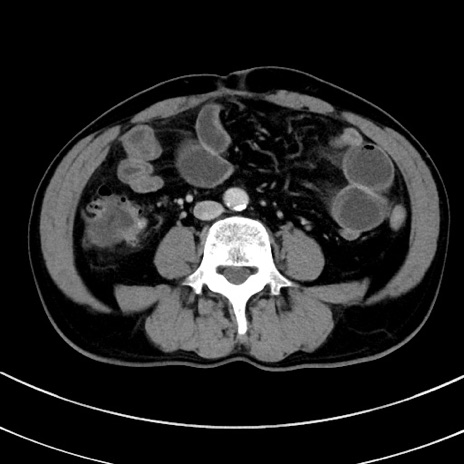

症例8(横断像)

【症例】 60歳代男性

【主訴】 黒色吐物

【現病歴】 4日前から嘔気自覚、2日前の朝食後にも嘔気あり、自分で手で嘔吐反射起こし嘔吐したところ血が混ざっていたため受診。

【既往歴】 5年前汎発性腹膜炎を伴う急性虫垂炎で手術、高血圧、前立腺肥大症、高脂血症

【身体所見】 腹部正中に手術癩痕あり 腹部平坦・軟圧痛なし膨満感あり

【データ】WBC 8400、CRP 4.54